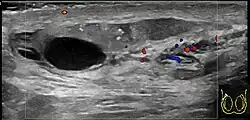

Scrotal ultrasound showing calcifications and cysts in a case of chronic epididymis.

Chronic epididymitis is a form of epididymitis that persists for more than three months. Chronic epididymitis is characterized by inflammation even when there is no infection present. Tests are needed to distinguish chronic epididymitis from a range of other disorders that can cause constant scrotal pain, including testicular cancer (though this is often painless), enlarged scrotal veins (varicocele), calcifications,[15] and a possible cyst within the epididymis. Some research has found that as much as 80% of visits to a urologist for scrotal pain are for chronic epididymitis.[4]: p.311  As a further complication, the nerves in the scrotal area are closely connected to those of the abdomen, sometimes causing abdominal pain similar to a hernia (see referred pain).